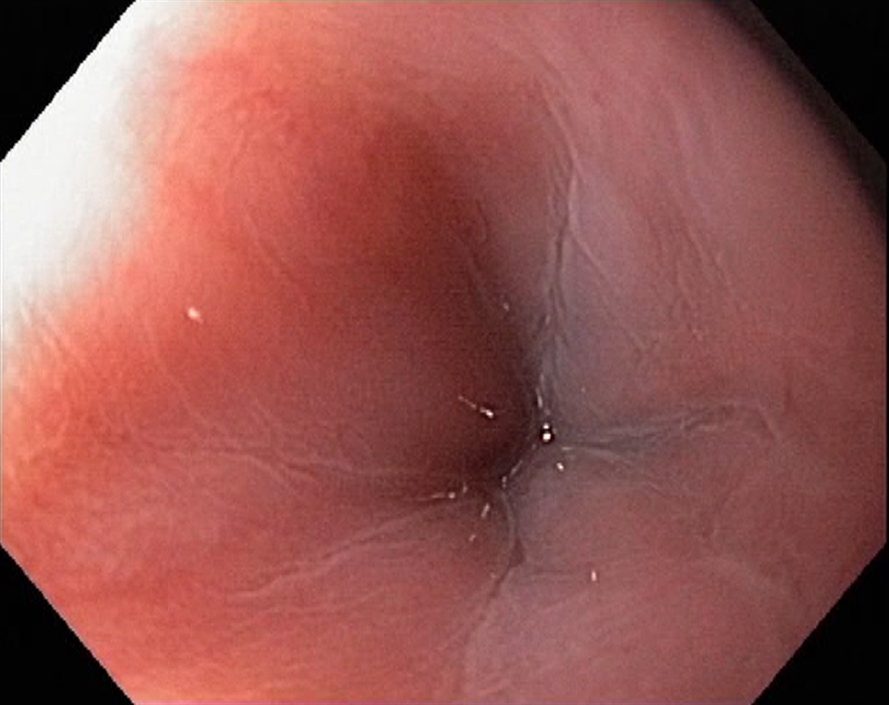

Achalasia cardiae is a motility disorder of the oesophagus, where there is a nerve degeneration in the Auerbach´s plexus, causing inability of the lower oesophageal sphincter in the cardia region (C) to relax. In oesophageal x-ray examanations a dilatation of the oesophagus is seen, and the contrast stays in the oesophagus for a long time. Endoscopy shows a quite normal cardia, and in less severe cases the endoscopic diagnose is not easy. Dysphagia is the main symptom, causing weight loss in severe cases. Achalasia can be treated with medicines (nifedipine, nitrates), botulinumtoxin injections in the cardia, dilatation during endoscopy and surgically (Heller´s myotomy).